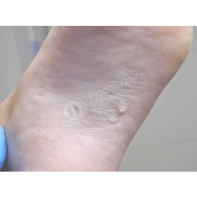

В вопросе, скорее, речь идет о синдроме оплывшего дистального валика, что является проявлением ониходистрофии, и может появляется после отслоения ногтевой пластины на фоне длительного давления или травмы, а также после длительного отсутствия ногтевой пластины после ее удаления. В таком случае ногтевое ложе остается частично не прикрытым, и кожа дистальной части околоногтевого валика, накрывает оголенное ложе. Тем самым ногтевая пластина, отрастая, встречает «преграду» в виде валика и травмирует его.

В данном случае необходима чистка ногтевой пластины и установка коррекционных систем. Иногда подолог может установить тампонады или протезирующий материал для поднятия ногтевой пластины над ложем. Все зависит от клинической картины и выраженности закрытия ложе дистальным валиком. Данные манипуляции проводятся 1 раз в 2-4 недели, сроки так же зависит он выраженности клинической картины.